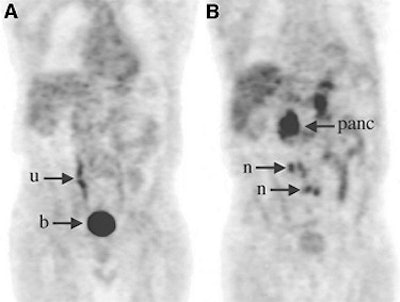

| Above, a 77-year-old man with PSA relapse and a serum PSA value of 10.5 ng/mL. The patient underwent radical prostatectomy and salvage external-beam radiation. The coronal FDG-PET image (A) showed only urinary activity in the right ureter (u) and bladder (b). The AC-PET (B) image indicates high uptake in the multiple paraortic lymph nodes (n), and normal uptake in the pancreas (panc). Image and caption courtesy of Dr. Nobuyuki Oyama and the Journal of Nuclear Medicine. |